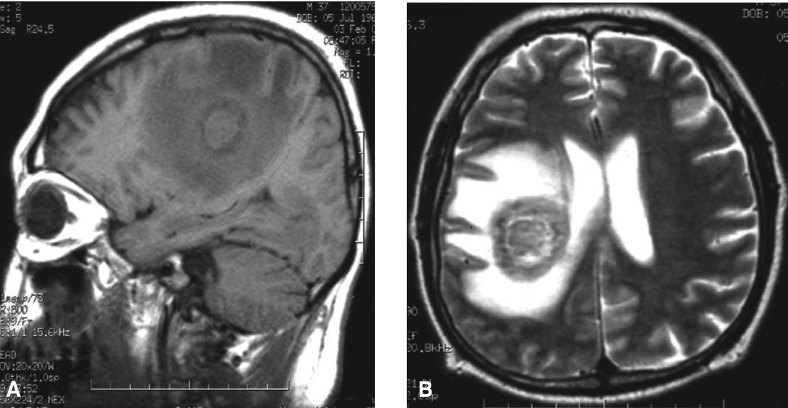

A 37-year-old male was admitted to our hospital because of his left sided hemiplegia that he had experienced for 3 months. He was known to be positive for HIV, as was determined during evaluation for idiopathic thrombocytopenic purpura in a foreign country about 6.5 years before this admission. At that time, he had been treated with zidovudine, lamivudine and saquinavir for the management of AIDS for 9 months and then he discontinued therapy of his own will. He was advised to restart treatment with zidovudine, lamivudine and indinavir at our hospital 4 years ago. He noticed weakness on the left side of his body during movement, which had slowly progressed and he finally developed left-sided hemiplegia 3 months previously. At the time of admission, he had complaints of headache and night sweats. He was diagnosed as having idiopathic thrombocytopenic purpura about 6.5 years ago and so splenectomy was done. Even after splenectomy, the thrombocytopenia continued. He was treated with steroid, vincristine, intravenous gammaglobulin, rituximab and danazole. He had also experienced liver abscess 4 years ago. He had received radiation for Kaposi sarcoma about 8 months before admission. On admission, the blood pressure was 90/60 mmHg, the pulse rate 100/min, the respiration rate 22/min and the body temperature was 38℃. Upon physical examination, the patient was in poor general condition with anemic conjunctiva. There were no signs of hemorrhagic diathesis or icterus. The laboratory finding were as follows; hemoglobin 7.4 g/dL, WBC 8,300/mm3 (neutrophila: 79.5%, lymphocytes: 14.6%, monocytes: 4.6%), platelets 10,000/mm3, erythrocyte sedimentation rate (ESR) 2 mm/h, AST 24 IU/L, ALT 9 IU/L, total bilirubin 0.7 mg/dL, LDH 473 IU/L, protein 3.9 g/dL, albumin 2.3 g/dL, BUN 9.5 mg/dL, creatinine 0.42 mg/dL, calcium 7.3 mg/dL, phosphorus 3.1 mg/dL, Na 130 mmol/L, K 3.0 mmol/L, the total number of CD4 and CD8 T lymphocytes was 46/mm3 and 621/mm3, respectively, and the ratio of CD4/CD8 was 0.07. The chest X-ray was not remarkable. Brain MRI (Figure 1A) shows 4 cm-sized round mass involving the right frontal lobe. The T1 weighted image and the T2 weighted image (Figure 1B) showed extensive areas of perilesional edema involving the right frontoparietal region and there was a mass effect upon the right lateral ventricle. Stereotactic biopsy of the brain lesion was performed, and histological examination disclosed atypical lymphoid cells with a predominant perivascular arrangement (Figure 2). Immunohistochemical examination showed positivity for CD20. The diagnosis of diffuse large B-cell lymphoma involving the CNS was made. The patient was treated with brain radiation. Sadly, he died of pneumonia 13 days after brain radiation therapy.

(A) Brain MRI shows a 4cm sized round mass involving the right frontal lobe. (B) The T2 weighted image shows extensive areas of perilesional edema involving the right frontoparietal region and there is a mass effect upon the right lateral ventric